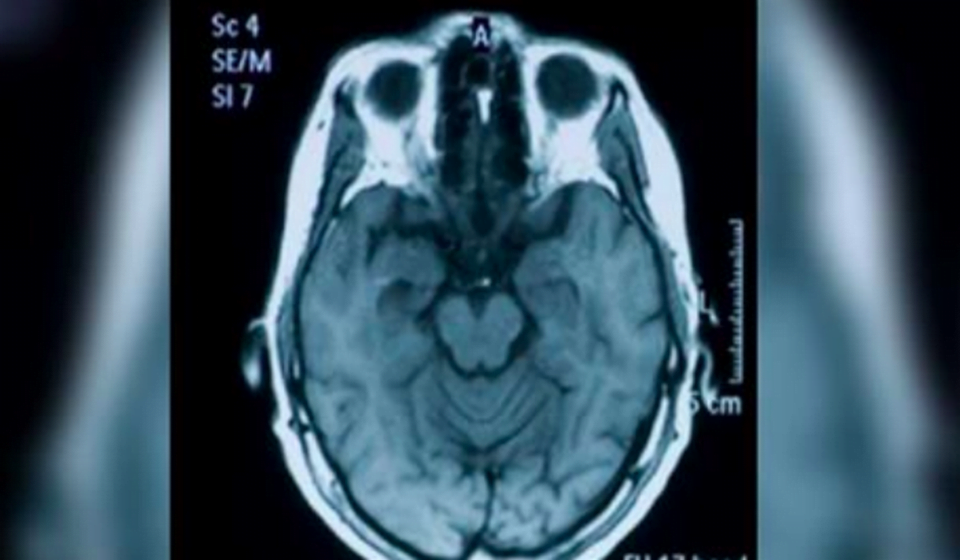

I ricercatori hanno studiato anni e anni di memoria selettiva e funzionamento del cervello, sia nell’uomo che negli animali.

Secondo gli scienziati, dimenticare i dettagli che non sono importanti aiuta a prendere decisioni nella vita quotidiana e consente anche connessioni neurali che sovrappongono nuove conoscenze a quelle vecchie. Cioè, il meccanismo consente la possibilità di incorporare nuove conoscenze e adattarsi più facilmente a situazioni inaspettate.

Secondo i ricercatori, dimenticare i dettagli è sano e necessario, perché altrimenti il cervello immagazzinerebbe ricordi irrilevanti che sarebbero in conflitto con le informazioni di cui abbiamo bisogno per prendere le decisioni che influenzano le nostre vite. La dimenticanza occasionale è un segno che la nostra memoria è in buone condizioni.

Ecco perché è importante che il cervello dimentichi i dettagli irrilevanti e si concentri su ciò che serve per prendere decisioni nel mondo reale”, ha affermato Richards. Lui, insieme al suo collega di ricerca Paul Frankland, è sicuro che ciò che dimenticano è un meccanismo di sicurezza del cervello per evitare il sovraccarico di informazioni.

Un altro motivo per cui la memoria dimentica certi dati degli eventi passati è perché ha la capacità di ricordare un’immagine in generale. I ricercatori sostengono che il meccanismo ha lo scopo di darci la possibilità di applicare queste memorie in modo più efficace in situazioni che si verificano nel momento presente.